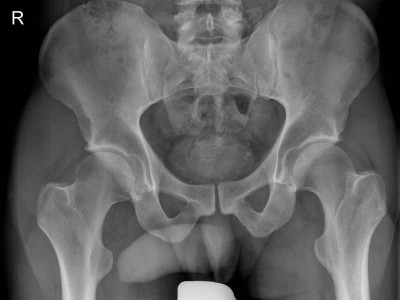

Pincer-Impingement und Coxarthrose: Auf den CE-Winkel kommt es an!

Das sogenannte Beißzangen-Impingement des Hüftgelenks war in einer großen Kohortenstudie mit einem signifikant höheren Risiko für eine spätere Coxarthrose assoziiert – allerdings nur dann, wenn ein bestimmter Wert beim CE-Winkel überschritten wurde.

Pincer-Konstellation, Hüftdysplasie und CAM-Impingement im Röntgenbild/© Fehske K / all rights reserved Springer Medizin Verlag GmbH, Sonographiequerschnitt über der Hälfte des M. quadriceps (Normalbefund)/© Gehlen M et al. / all rights reserved Springer Medizin Verlag GmbH, Mediale Meniskusallografttransplantation /© Winkler PW et al. doi.org/10.1007/s43205-025-00320-y unter CC-BY 4.0, Sehnentransplantate zur Rekonstruktion des vorderen Kreuzbands /© Fink C et al. doi.org/10.1007/s00113-025-01551-4 unter CC-BY 4.0, Knie-MRT zeigt überlastungsbedingte Knochenmarködeme/© Brockmeyer M et al. / all rights reserved Springer Medizin Verlag GmbH, Läufer umfasst sein Sprunggelenk/© PeopleImages / Getty Images / iStock (Symbolbild mit Fotomodell), Gruppe beim Rückentraining im Fitnesscenter/© Robert Kneschke / stock.adobe.com (Symbolbild mit Fotomodellen), Walking mit Kniebandage/© Suzi Media Production / Getty Images / iStock (Symbolbild mit Fotomodell), Vordere Kreuzbandruptur/© Springer-Verlag Berlin Heidelberg 2016, Operation zum Kniegelenkersatz/© Issara / stock.adobe.com, Ein kleines Kind hüpft auf einem Trampolin/© anzebizjan / stock.adobe.com (Symbolbild mit Fotomodellen), Anteriore Schulterluxation im Röntgenbild/© Spagna G et al. / all rights reserved Springer Medizin Verlag GmbH, Laufschuh binden/© ssoil322 / stock.adobe.com, Hämatom an der Stirn des 9-Jährigen/© Dr. med. Thomas Hoppen, Innenseitige Hauteinziehung bei eingeschlagenem Innenband/© Akalin ER et al. / all rights reserved Springer Medizin Verlag GmbH, Rekonstruktion der Halswirbelsäule im CT/© Prof. Klaus Schunk, Sonografie am Fußgelenk/© A. Schuh, Gebrochener Fuß im Gips/© Aleksandr Kirillov / stock.adobe.com (Symbolbild mit Fotomodell), Search Icon, Arthropedia, Frau unkenntlich fasst sich ans Knie/© Pornpak Khunatorn / Getty Images / iStock (Symbolbild mit Fotomodell), Ärzteteam führt Hüftoperation durch/© ATRPhoto / stock.adobe.com (Symbolbild mit Fotomodell)